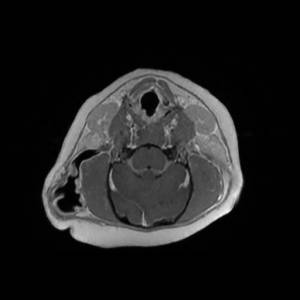

Main Gallery

Playing with a photo gallery function. It is possible to have multiple galleries, each within a namespace.